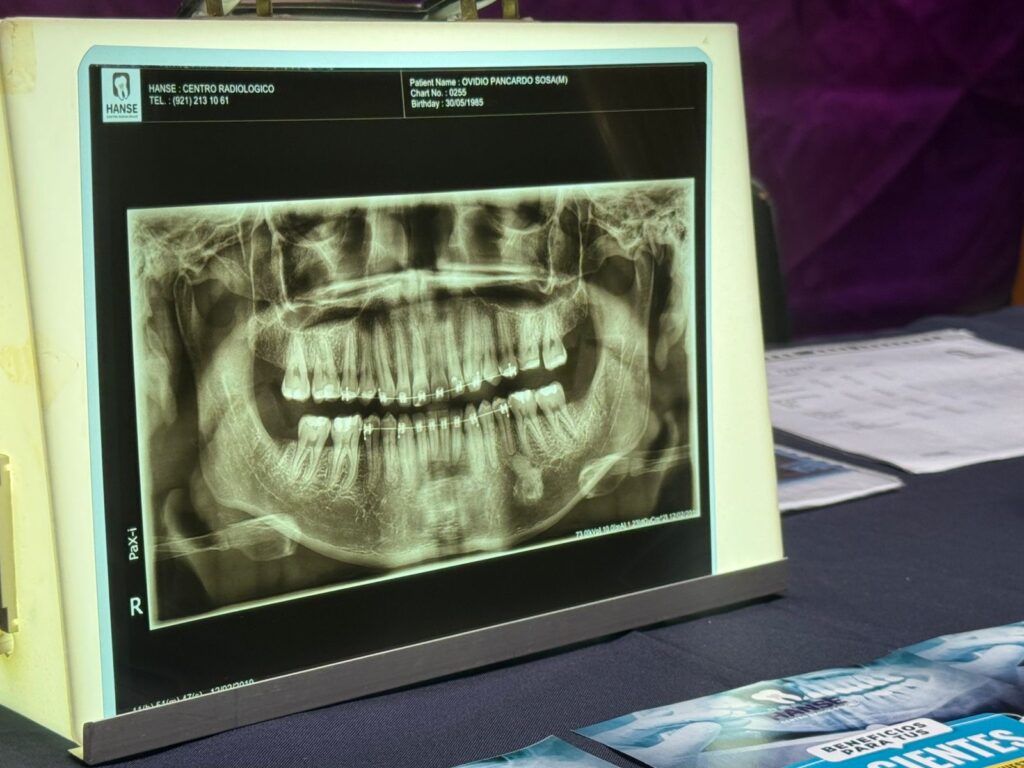

El presidente de la Asociación Dental de Coatzacoalcos, Alberto Ramos Jiménez, explicó que el consumo de estos productos, traen consecuencias que van desde desgaste del esmalte, problemas en las encías, en el caso de las bebidas, mientras que con los cigarrillos el deterioro es peor, pues enferma todo, desde los dientes, garganta y lengua.

En cuanto a las bebidas azucaradas hay una desmineralización en el esmalte, hay problemas que se causan en las encías también, precisamente por el exceso en el consumo, como en la leyenda, el consumo en exceso de la bebida causa problemas. La población mexicana piensa que con que se lave una vez en el día es suficiente. Tenemos que cuidar esa parte. En cuanto al tabaco, ahí si hay más problemas, no solo causa enfermedades pulmonares, problemas de pigmentación y micro fracturas, cáncer de boca”, indicó.

Una de las varias ponencias que tuvieron en el Centro de Convenciones, fue dirigida hacia las enfermedades crónico degenerativas y cómo estas pueden ser detectadas por los dentistas a fin de favorecer la atención de los pacientes.